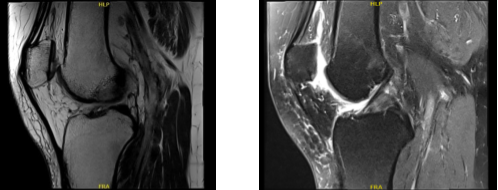

We agreed to go with 3 tesla MRI of Right knee, the results were reviewed and discussed by the doctor, there is no acute fracture or osteonecrosis. The Ligaments, cruciate and collateral ligaments are intact, the Lateral compartment meniscus demonstrates a partially discoid configuration.

There is a partial superior articular surface tear within the anterior horn of the lateral meniscus (sagittal image 14). No full-thickness cartilage defect is seen, there is tiny marginal osteophytosis.

Medial compartment is intrasubstance degenerative signal within the body and posterior horn of the medial meniscus without extension to an articular surface to constitute tear.

Mild free edge margin fraying is noted. There is mild to moderate thinning of the central weight bearing cartilage with focal full-thickness delamination at the medial femoral condyle where there is mild marginal edema.

The Patellofemoral compartment is moderate thinning overlying the central and medial trochlear cartilage with an 8 mm near full-thickness cartilage defects. There is an additional full thickness cartilage fissuring at the median ridge of the patella spanning 3 x 6 mm with a nondisplaced cartilage flap.

Muscle/tendon, the periarticular muscles are maintained. The imaged tendons, inclusive of the extensor mechanism, are intact. Joint fluid: There is a small-moderate joint effusion. No popliteal cyst is seen. There are no intra-articular ossific loose bodies. Mild anterior subcutaneous edema is noted.

The neurovascular structures demonstrate normal course. Partial anterior lateral meniscus tear. Moderate medial compartment cartilage wear. Tricompartmental cartilage wear with full-thickness loss most notably at the patellofemoral compartment where there is a 6 mm nondisplaced patellar cartilage flap.

MRI-3T Right knee non-contrast